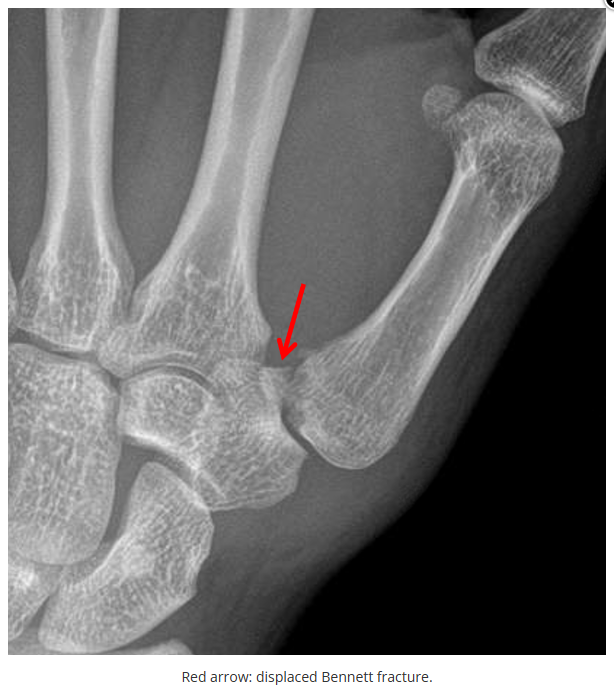

这些腕与手的骨折X线片如果没有标注箭头,你还能识别出来吗?

X线读片是骨科医生的基本功。

今天是腕部与手的X线片。所有X线片都

带有标注和说明

,可以选择长按图片,

自动翻译相关说明